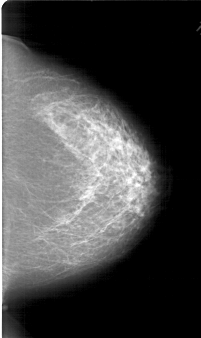

A_1789_1.LEFT_CC

LEFT_CC LINES 6871 PIXELS_PER_LINE 3706 BITS_PER_PIXEL 12 RESOLUTION 43.5 OVERLAY

FILE: A_1789_1.LEFT_CC.OVERLAY

TOTAL_ABNORMALITIES 1

ABNORMALITY 1

LESION_TYPE MASS SHAPE LOBULATED MARGINS OBSCURED

ASSESSMENT 4

SUBTLETY 3

PATHOLOGY BENIGN

TOTAL_OUTLINES 1

BOUNDARY